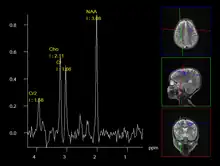

MR spectroscopy (MRS) of the brain to identify different chemical components based on their unique resonant frequencies.

A less intrusive alternative imaging technique is magnetic resonance spectroscopy (MRS), which is used to determine the chemical compositions of cells. However, it is not as reliable as biopsies.[12]